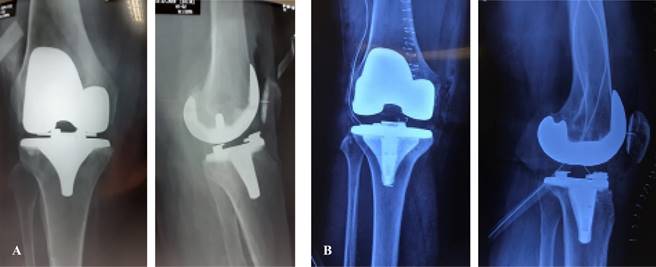

Los dos tipos de prótesis que más se utilizan en la actualidad son la prótesis total de rodilla con preservación del ligamento cruzado posterior y la posteroestabilizada o con sustitución del ligamento cruzado posterior (Figura 1). Se presenta un estudio comparativo, descriptivo y multicéntrico que valora los resultados funcionales entre pacientes que utilizan la retención o sustitución del ligamento cruzado posterior en nuestro medio.